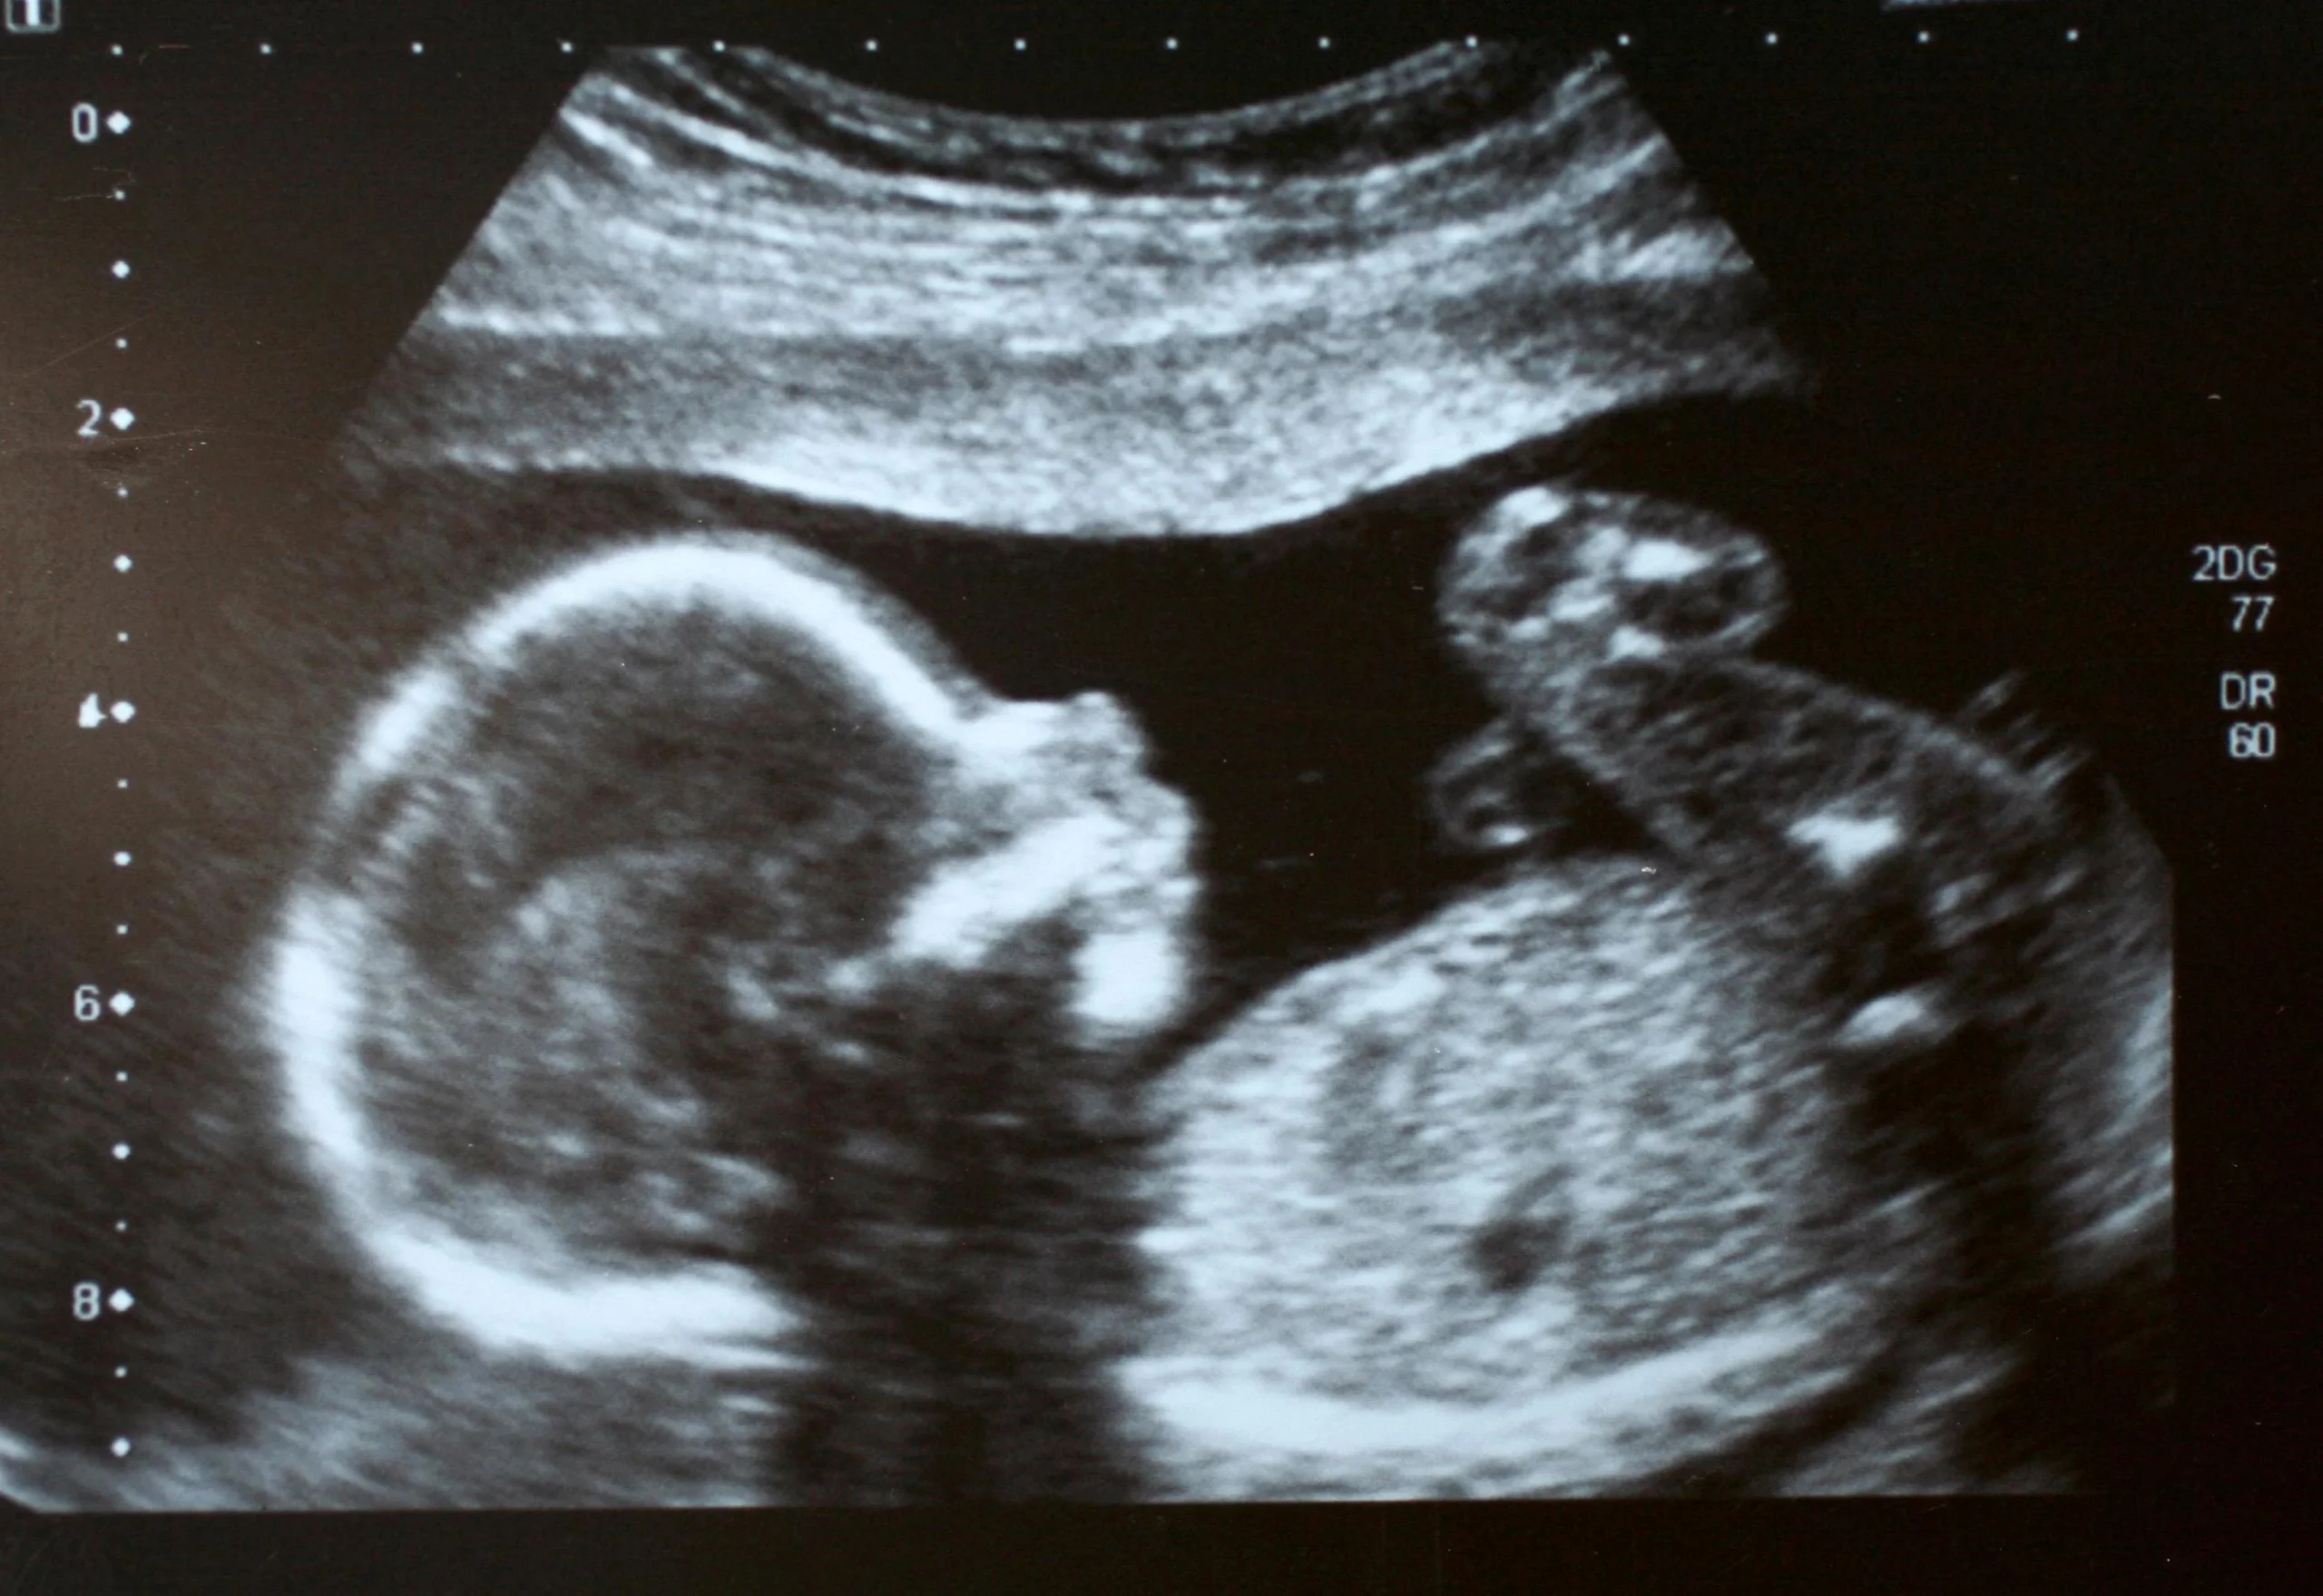

Im letzten Trimester der Schwangerschaft kann der Ultraschall wichtige Informationen über den Gesundheitszustand des Kindes und die Entwicklung der Schwangerschaft liefern.

Zu den Informationen, die der Ultraschall im letzten Trimester liefern kann, gehören:

- Die Größe und das Gewicht des Kindes

- Die Lage des Kindes im Bauch

- Die Menge des Fruchtwassers

- Die Plazenta-Lage und -Funktion

- Der Nabelschnurfluss

- Die Entwicklung der Organe des Kindes

Die Ergebnisse des Ultraschalls können dem Arzt/der Ärztin helfen, die weitere Vorgehensweise in der Schwangerschaft zu planen. Wenn zum Beispiel die Menge des Fruchtwassers zu gering ist, kann eine zusätzliche Kontrolle notwendig sein.